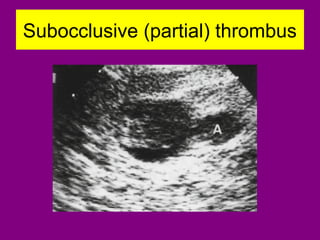

Subocclusive (partial) thrombus